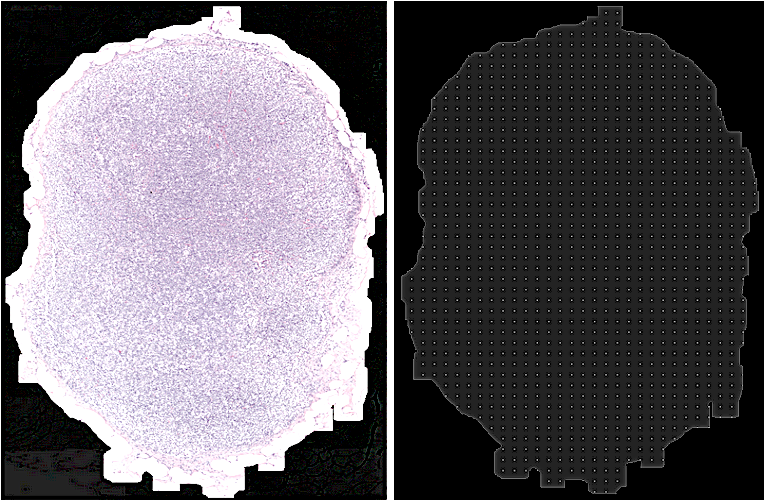

3.8 Inference pipeline

The pre-processing step in the inference pipeline included segmentation of tissue region from the whole slide image (refer 3.3.1). In order to facilitate extraction of patches from the whole slide image within the tissue mask region, a uniform patch-coordinate sampling grid was generated at a lower resolution, as shown in Figure 5. Each point in the patch sampling grid was re-scaled by a factor to map to the coordinate space corresponding to the whole slide image at its highest resolution. From these scaled coordinate points as the centre, fixed-size high-resolution image patches were extracted from the whole slide image for feeding the trained segmentation model’s input. The sampling stride was defined as the spacing between consecutive points in the patch sampling grid. The patch size and the sampling stride controlled the overlap between consecutive extracted patches from the whole slide image. The main drawback of patch-based segmentation method for whole slide image was that the smaller patch sizes could not capture wider context of the neighbourhood region. Moreover, stitching of the segmented patches introduced boundary artefacts (blockish appearance) in the tumour probability heatmaps. The generated heatmaps were smooth when the inference was done on overlapping patches with larger patch-size and averaging the prediction probabilities at the overlapping regions. The experimental observation suggested that 50% overlap between consecutive neighbouring patches was the optimal choice as it ensured that a particular pixel in a whole slide image was seen at most 4-times during the heatmap generation. However, this approach increased the inference time by a factor of 4. Also, during inference, increasing the patch size by a factor of 4 (1024x1024) when compared to the patch size used during training (256x256) improved the quality of generated heatmaps.